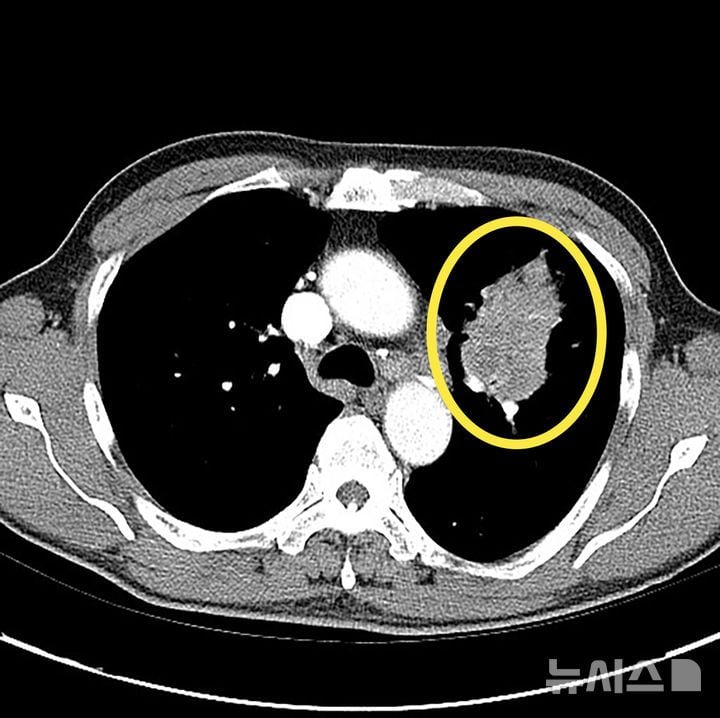

폐암 수술이 생존률만이 아니라, 수술 후 환자 삶의 질까지 중시하는 정밀 맞춤 치료로 빠르게 진화하고 있다. 최근 저선량 흉부 CT(Computed Tomography) 검진이 보편화되면서 2㎝ 이하 ‘조기 폐암’ 발견이 급증했고, 이에 따라 정상 폐 조직을 최대한 살리는 구역절제술·쐐기절제술 등 정밀 수술이 새로운 치료 표준으로 자리잡고 있다. 업계는 이같은 변화가 폐암 치료 경쟁의 분기점이 될 것으로 보고, 수술 이후 환자 회복과 일상 복귀까지 아우르는 수술법 개발에 역량을 집중하는 분위기다.

최근 발표된 의료계 자료에 따르면 저선량 CT 도입 후 종양 크기가 2㎝ 이하인 폐암 환자 비율이 크게 증가했다. 이에 따라 기존 폐엽 전체 절제 방식의 광범위 수술 대신, 암이 위치한 폐의 ‘구역’만 선별적으로 제거하는 구역절제술이 도입됐다. 구역절제술은 전체 엽을 남겨두는 것이 특징으로, 기존 절제술 대비 폐 기능을 5~10% 더 보존할 수 있다는 분석이다. 이는 환자가 수술 후 계단 오르기나 운동 시 호흡 곤란을 덜 겪고, 회복 기간을 앞당기는 것으로 평가된다.

핵심 원리는 폐를 최소 단위인 구역(세그먼트)으로 나눠 병변이 있는 곳만 절제하는 데 있다. 더 소규모인 쐐기절제술은 암 주변 조직만 삼각형 모양으로 잘라낸다. 이런 방식은 정상 폐 조직을 최대 90%까지 보존할 수 있도록 설계돼, 그만큼 폐의 기능 유지가 용이하다. 미국·일본 등 주요 선진국 연구에서도 구역절제술의 5년 생존률과 재발률이 기존 광범위 수술과 차이가 없다는 대규모 임상 결과가 제시돼, 조기 폐암에선 표준 치료가 되고 있다.